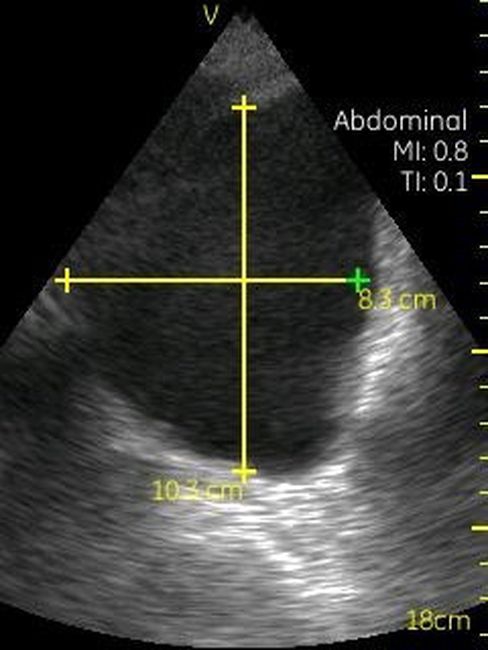

Визуализация Vscan:

· Черно-белый режим для визуализации анатомических структур в реальном времени.

· Поле зрения в черно-белом режиме: до 75 градусов с максимальной глубиной 25 см.

· Широкополосный фазированный датчик с частотой от 1,7 до 3,8 МГц.